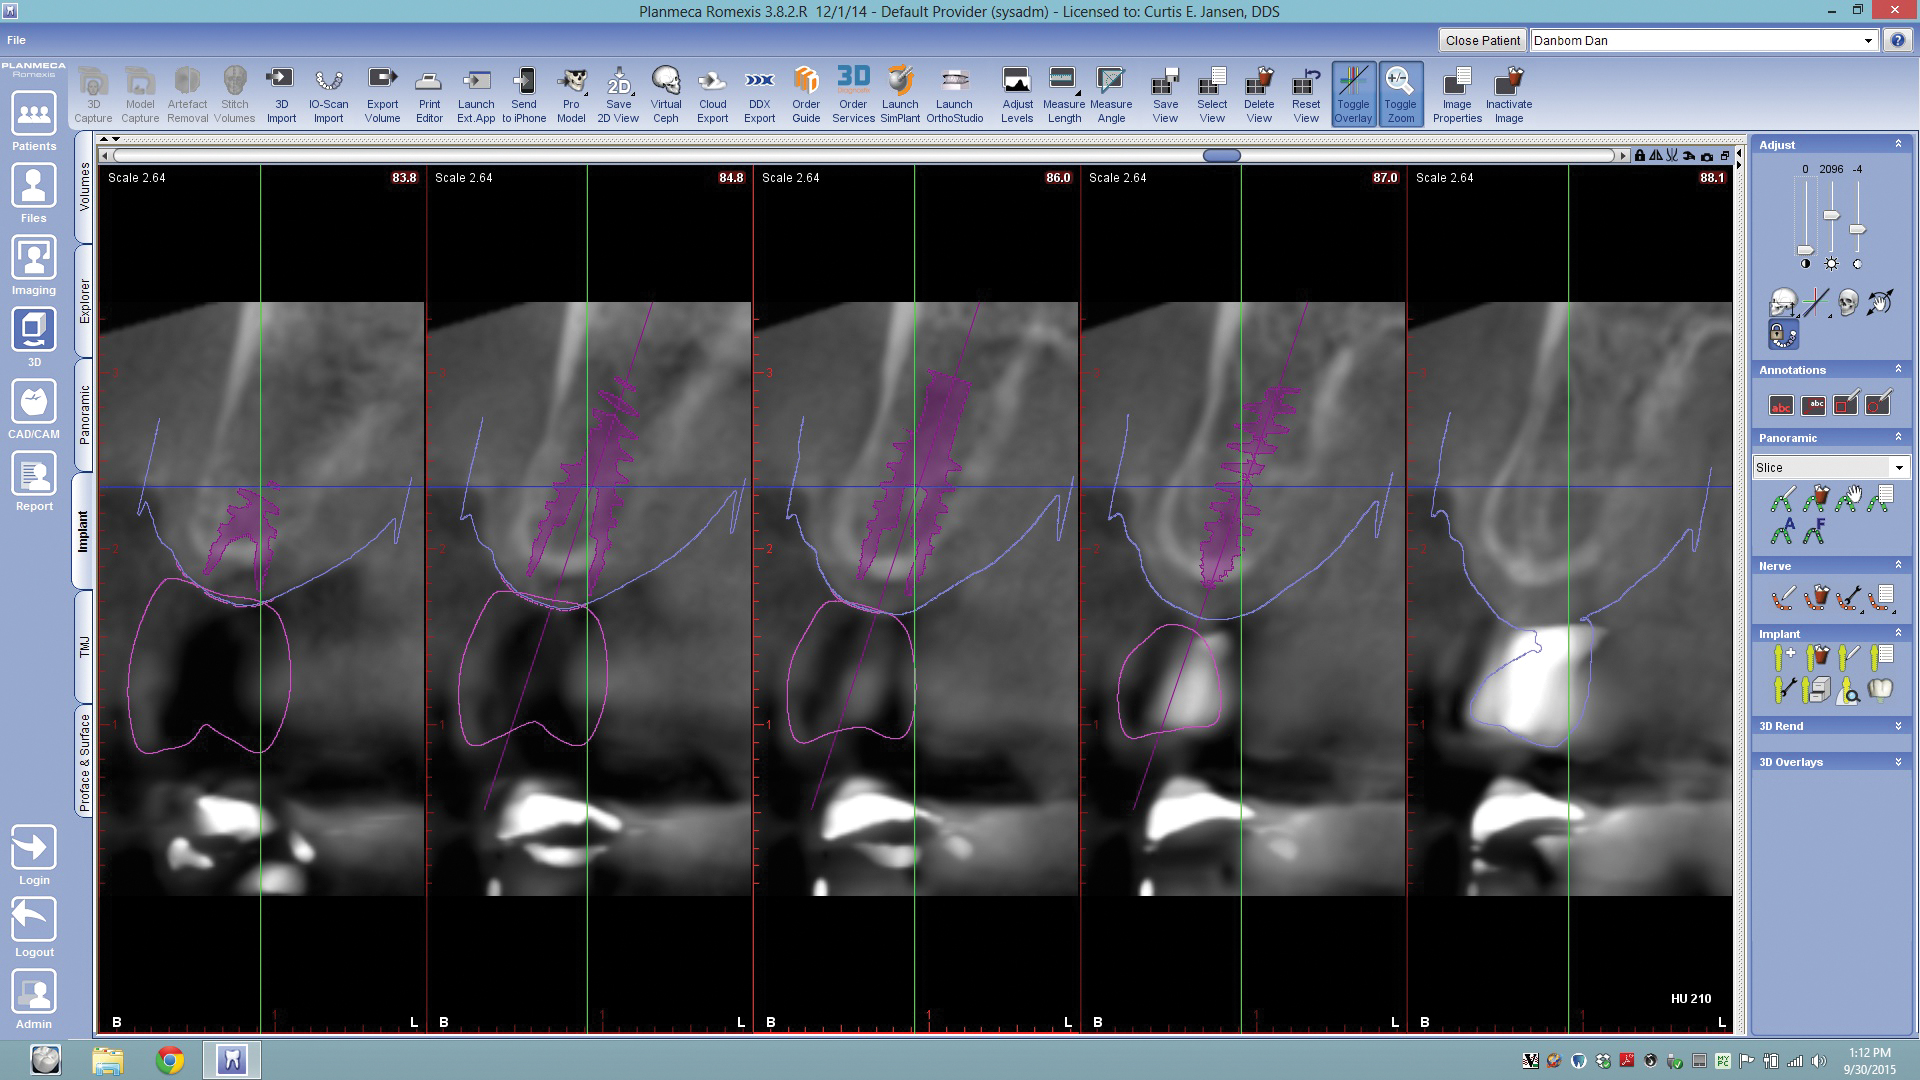

Fig 10. By merging CBCT files with IOS files and using implant planning software, dental professionals can plan all components of the implant/restoration procedure in advance for a restoratively driven approach: CBCT, IOS, and CAD merged and overlayed as one (Fig 9); implant placement and implant guide CAD (Fig 10).

Figure 10